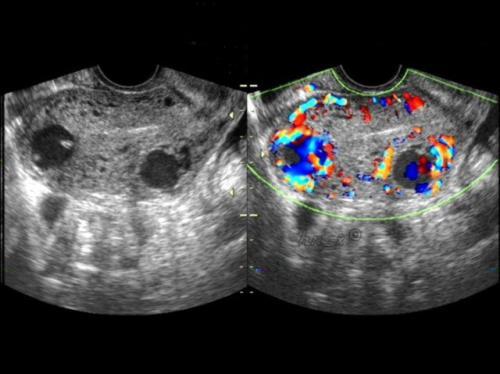

B超看见的卵巢囊肿主要分两类,一类是生理性囊肿,也就是正常的囊肿,这种囊肿包括卵泡囊肿 黄体囊肿。第二类是病理性囊肿,病理性囊肿提示卵巢和输卵管可能有疾病。需要进一步诊断和治疗。

黄体囊肿也就是卵泡把卵子排出来了,剩下来的组织就形成了黄体。黄体囊肿特点里面回声有点杂,B超会经常描述成混合性回声。如果当月排出来的卵没有怀孕,那黄体囊肿就没有任务了,就自行萎缩掉。如果怀孕了,黄体囊肿继续增大,分泌更多的孕酮维持妊娠。这时候黄体囊肿的名字就变成了妊娠黄体。

这些囊肿的特点是月经干净后复查,囊肿不会缩小,大小不变或会增大。或者B超下看上去回声乱糟糟。这些囊肿需要及时的治疗。